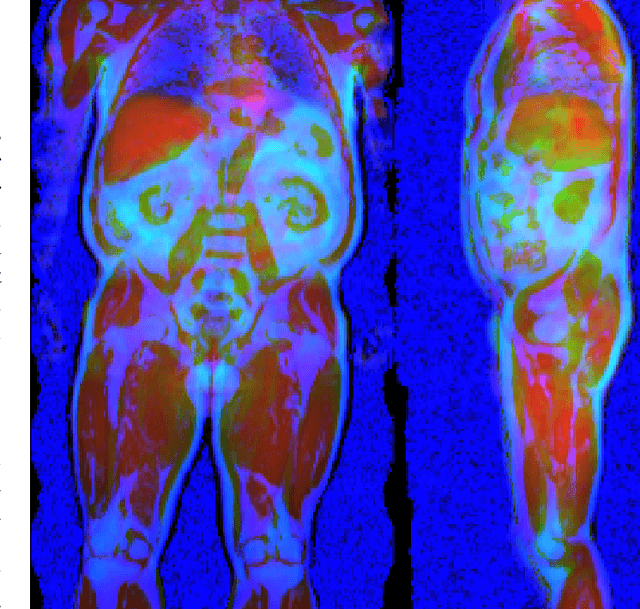

Abstract:Large-scale medical studies such as the UK Biobank examine thousands of volunteer participants with medical imaging techniques. Combined with the vast amount of collected metadata, anatomical information from these images has the potential for medical analyses at unprecedented scale. However, their evaluation often requires manual input and long processing times, limiting the amount of reference values for biomarkers and other measurements available for research. Recent approaches with convolutional neural networks for regression can perform these evaluations automatically. On magnetic resonance imaging (MRI) data of more than 40,000 UK Biobank subjects, these systems can estimate human age, body composition and more. This style of analysis is almost entirely data-driven and no manual intervention or guidance with manually segmented ground truth images is required. The networks often closely emulate the reference method that provided their training data and can reach levels of agreement comparable to the expected variability between established medical gold standard techniques. The risk of silent failure can be individually quantified by predictive uncertainty obtained from a mean-variance criterion and ensembling. Saliency analysis furthermore enables an interpretation of the underlying relevant image features and showed that the networks learned to correctly target specific organs, limbs, and regions of interest.